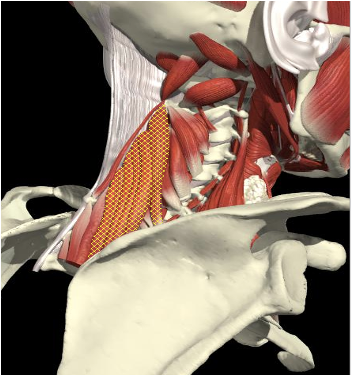

Levator Scapulae

Origin

First to the fourth cervical vertebrae.

Insertion

Medial edge of the scapula, between the superior angle and the root of the spine.

Action

- Acts as a checkrein for the bent head

Levator Scapulae & Neck Motion

Left Lateral Flexion

Left U Trapezius, SCapitus and Levator Scapulae

Left U Trapezius,

Right SCapitus , Levator Scapulae

Bilateral U Trapezius

Scapitus, Levator Scapulae

Right Rotation

Extension